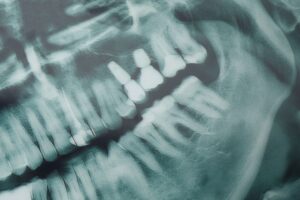

Full mouth dental implants in Minneapolis, Minnesota are a comprehensive solution for individuals who have lost most or all of their teeth. Full mouth dental implants give patients a fixed, more stable alternative to dentures. The full mouth dental implant procedure involves the strategic placement of titanium dental implant posts into the patient’s jawbone, which act as artificial ‘roots’ for the new teeth.

During a full mouth dental implant procedure, the dental professional will first administer sedation dentistry to the patient. With sedation dentistry, patients will have a comfortable and anxiety-free procedure experience. Once the sedation dentistry option takes effect, the dental professional accurately and securely places the full mouth dental implants in the patient’s mouth.

A temporary prosthesis can then be attached to the full mouth dental implants while the final prosthesis is being made. When the final prosthesis is ready, they are attached to the full mouth dental implants. The result is a fully restored, natural-looking, and functional set of new and improved teeth. Sedation dentistry ensures that this entire full mouth dental implant procedure process is comfortable and manageable for the patient.